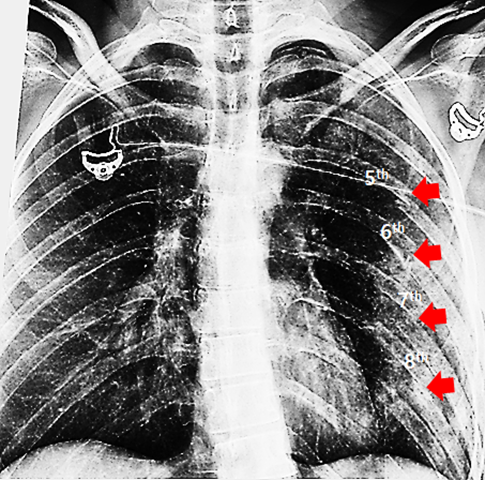

2. A chest radiograph was obtained upon arrival for initial assessment.

Multiple airspace opacities are observed in the left lung, adjacent to areas of acute rib fractures, suggesting underlying pulmonary laceration or contusion. In addition, a small-to-moderate left-sided pneumothorax is identified, evidenced by the presence of a white visceral pleural line at the apex.

Radiograph: Multifocal airspace opacities were noted in the left lung, adjacent to sites of acute rib fractures. A small to moderate left pneumothorax was also identified.